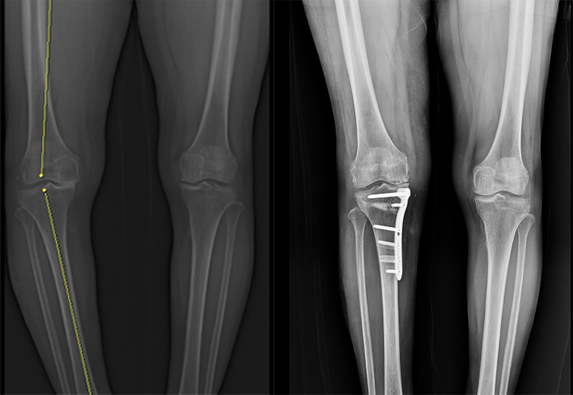

관절염 초기와 중기에는 인공관절 수술 대신 근위경골절골술을 고려해볼 수 있다.

이 원장은 "관절 모두를 긁어내야 하는 인공관절 수술과 달리

일부 관절을 보존할 수 있다는 장점이 있다"면서

"무릎에 실리는 하중을 골고루 분배해 퇴행성관절염의 속도를 늦출 수 있고,

수술 후 운동 범위를 보존하고 자유롭게 활동할 수 있다"고 설명한다.

주요 대상은 초·중기 퇴행성관절염과 함께 다리에 변형을 보인 환자다.

무릎 연골이 비교적 많이 남은 65세 미만에서는

개선에 도움을 받을 수 있다고 이 원장은 말한다.

근위경골절골술 후 회복에 걸리는 시간은 사람마다 다르지만 보통 2주 뒤에는 발을 디디는 데 문제가 없다.

이후 자전거 타기, 조깅 등 가벼운 스포츠 활동은

한 달 정도 비교적 짧은 재활 시간을 거치면 가능하다고 한다.